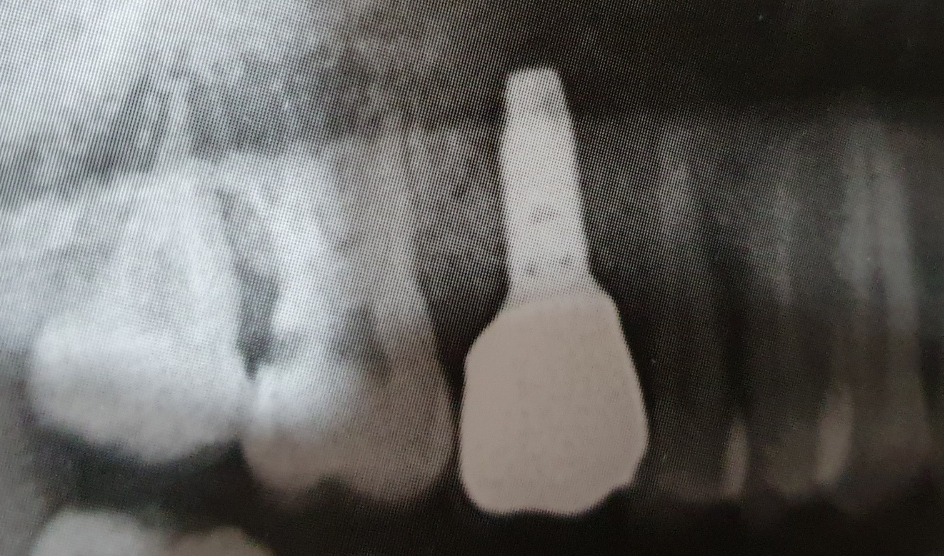

신논현역치과 중 임플란트 잘 하는 스마일뷰에서 임플란트를 완성하고 파노라마를 찍은 모습입니다.

신논현역치과 스마일뷰에서 임플란트를 식립하고 완성할 경우

임플란트치아는 위의 사진처럼 가운데에 홈을 남겨서

추후에 식립한 임플란트에 문제가 발생했을 경우 A/S를 수월하게 할 수 있도록 하고

마지막으로 본인의 치아처럼 잘 메꾸어 마무리 하게 됩니다.